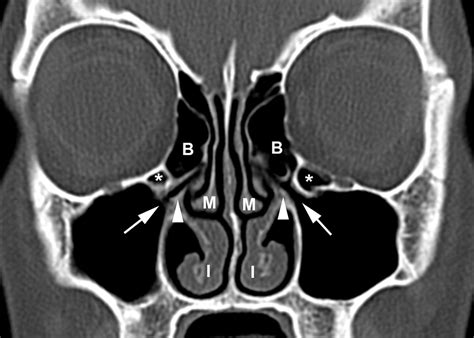

If you have been suffering from persistent sinus pressure, chronic congestion, or mysterious facial pain, your healthcare provider may recommend a Nasal CT scan to get a clearer picture of what is happening inside your nasal passages. This specialized imaging procedure is a cornerstone of modern otolaryngology, providing doctors with high-resolution, three-dimensional views of the complex structures within your nose and paranasal sinuses. Unlike a standard X-ray, which offers a two-dimensional look, a computed tomography (CT) scan provides detailed cross-sectional images, allowing specialists to pinpoint inflammation, structural abnormalities, or obstructions with remarkable accuracy.

The primary purpose of this imaging is to assist ear, nose, and throat (ENT) specialists in diagnosing conditions that cannot be easily visualized during a routine physical examination. Because the sinuses are deep within the skull, traditional physical inspections only show a small portion of the nasal cavity. A CT scan, however, reveals the entire network of sinuses, highlighting potential issues that may require medical or surgical intervention.

• Structural Abnormalities: Identifying a deviated septum or enlarged turbinates that might be causing breathing difficulties.

Once the images are captured, a radiologist will review them and generate a report. They look for specific markers of health, such as clear, air-filled sinus cavities, versus signs of pathology, such as fluid accumulation, mucosal thickening, or bone erosion. Your ENT specialist will then combine these results with your clinical symptoms to make a definitive diagnosis.